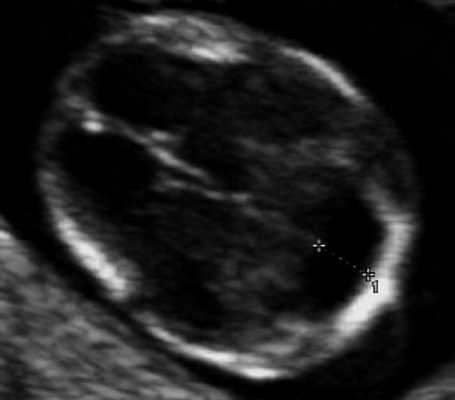

Рис. 7. Вентрикуломегалия у плода со spina bifida, беременность 12,4 недель.